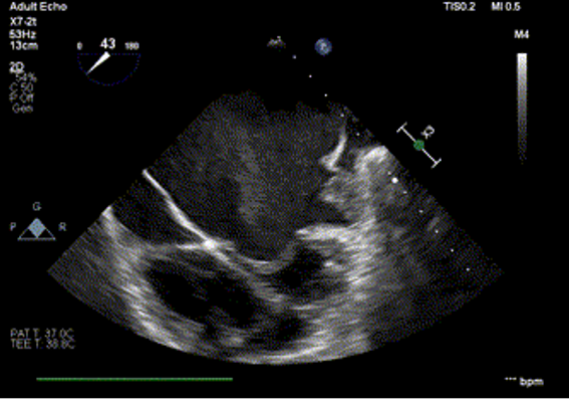

TEE: Type IB left atrial appendage thrombus, thin interatrial septum, no significant mitral regurgitation.

Given prohibitive surgical risk, high-risk BMV was attempted. Bilateral carotid angiography was performed and SpiderFx embolic protection devices (Medtronic, USA) deployed. Under TEE guidance, transseptal puncture was done, and an Inoue balloon (Toray, Japan) was advanced across the mitral valve. Sequential dilatations reduced the mean gradient with no embolic debris in filters. The patient improved hemodynamically and was discharged in stable condition.